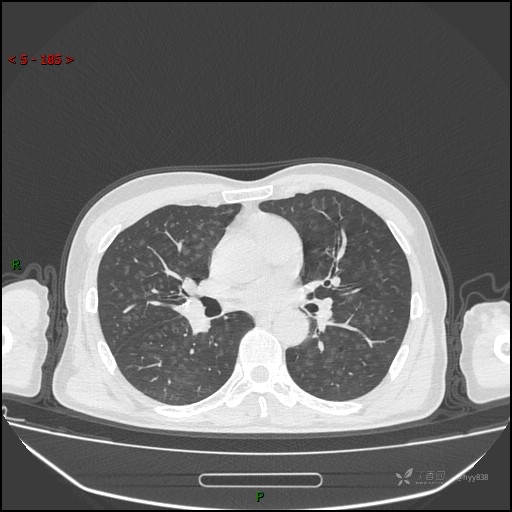

呼吸科电话会诊病例:过敏性肺炎 VS 吸烟相关间质性肺炎 VS 尘肺……结果公布~

性别:男

年龄:55岁

简要病史:渐进性呼吸困难。

胸部CT平扫

电焊工尘肺 (2)